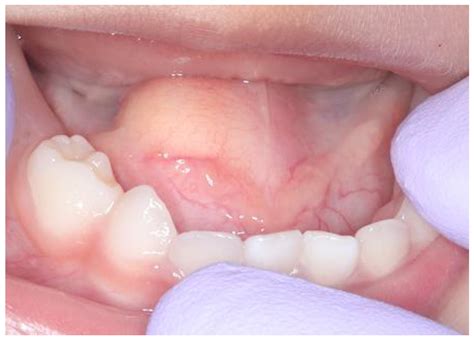

A dermoid cyst is a sac-like growth that contains various types of tissue, such as skin, hair, and sometimes even teeth or bone. These cysts are congenital, meaning they are present at birth, and can occur anywhere on the body. In infants, dermoid cysts are often found on the head, neck, or face, but they can also appear on the trunk or extremities.

• A small, firm lump under the skin

• In some cases, the cyst may be visible as a small, round bump on the skin